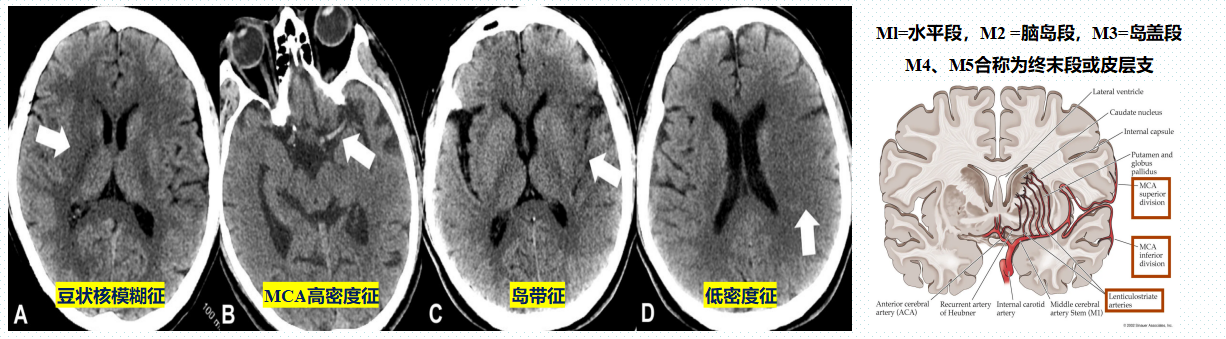

CT 表现:

豆状核模糊征:近端MCA闭塞使豆纹动脉血流受限所致

MCA高密度征:由于急性血栓形成,血流减慢甚至停滞所致;主干闭塞的征象。

岛带征:脑岛密度下降,与外囊结构区分不清所致;MCA岛段狭窄所致

低密度征:脑实质低密度、灰白质界限消失、脑回肿胀、脑沟变浅。

“大脑中动脉致密征”影像诊断陷阱。